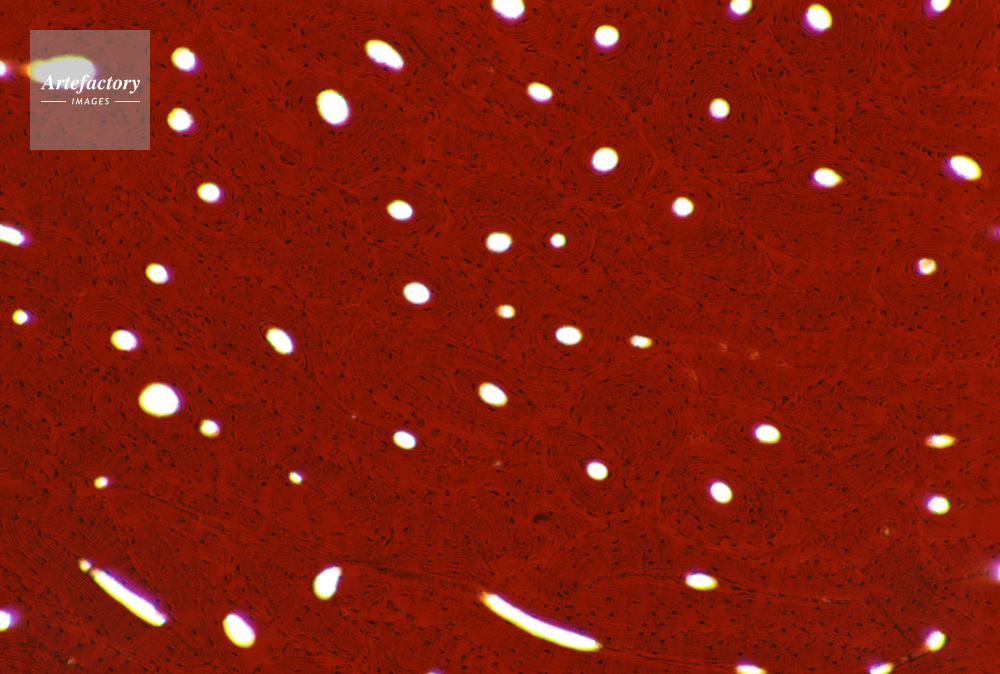

| 作品タイトル | 顕微鏡写真 | モデルリリース | なし | |

| キャプション | 硬骨,人間,40倍,横断面 | 制限事項 | ||

| ソース | ピクセル数 | 5577px × 3760px | ||

| 撮影地 | 印刷サイズ | 30.4cm × 20.5cm | ||